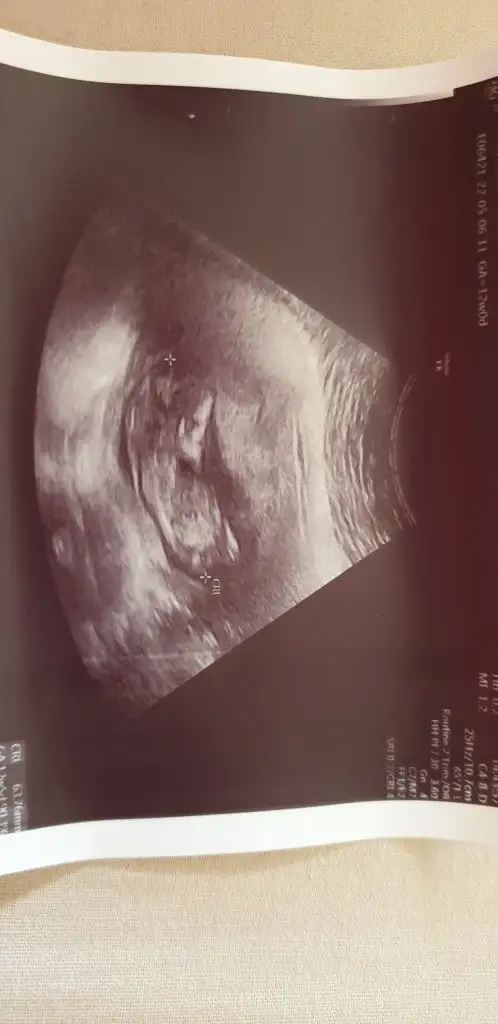

Canım benim de ultrason görüntüsü 6+3 bakabilir misin cinsiyet nedir şimdiden teşekkürler